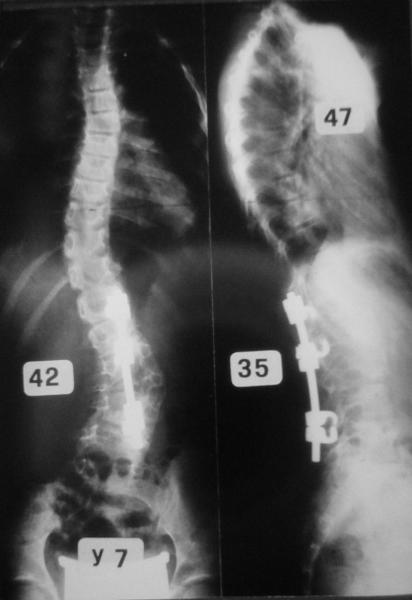

Il trattamento delle forme gravi di scoliosi idiopatica dell’adolescente, patologia più frequente nel sesso femminile, può richiedere un intervento chirurgico correttivo, che comprende una riduzione della deformità vertebrale, con apposizione di strumentario metallico, e la sua artrodesi, cioè la fusione dei metameri vertebrali interessati dalla curva. Il chirurgo vertebrale seleziona l’area da sottoporre ad intervento, per limitare una eccessiva rigidità a livello lombare, risparmiando il maggior numero di dischi intervertebrali caudali alla deformità (9,11). A volte, in presenza di gravi curve lombari, può essere però indispensabile estendere l’artrodesi a L4 o persino a L5. In questi casi è limitata la possibilità di flettere il tronco, e la forza del torchio addominale può essere diminuita (figura 3).

Occorre considerare inoltre come in un rachide sottoposto ad artrodesi vertebrale posteriore possa risultare impossibile l’accesso al canale vertebrale per l’esecuzione di una analgesia peridurale.